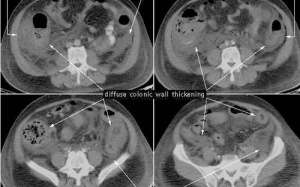

Làm thế nào để giữ cho đại tràng luôn khỏe mạnh?

Đại tràng đóng vai trò quan trọng trong quá trình tiêu hóa và hấp thu. Theo các chuyên gia từ Trung...

5 dấu hiệu ung thư đại tràng phổ biến dễ bị bỏ qua

Theo các chuyên gia y tế, nhiều triệu chứng ung thư đại tràng ở giai đoạn đầu thường rất...

Tại nước ta, ung thư đại – trực tràng là một trong những loại ung thư rất thường gặp và là nguyên nhân trực tiếp liên quan đến tử vong do ung thư. Vì vậy, phòng ngừa ung thư là phương...